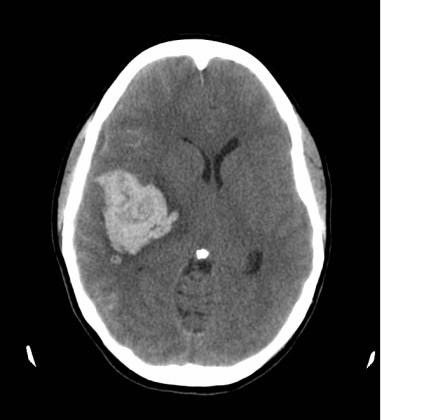

This is a slide from my first ct scan. I will do my best to explain what I learned about my ct scan.

A ct scan takes cross section images of the brain in layers. Doctors and Radiologists read these cross sections like a game of battleship to pinpoint the affected area and best course of action. This image is reversed. The left side of this image is actually the right side of the brain.

Note the following, when looking at this slide:

The skull bone is the white halo. At the “widow’s peak” of the skull bone, there is a fine white line(Midline Falx Cerebri) shifted towards the left.

2) The white cloud is located in the right side of the brain, the black butterfly looking thing is on the left side.

3) Apart from the skull bone, white in a brain ct scan is a bad thing. The white cloud is the blood clot. The white bumpy texture is blood in the subarachnoid space, (the space between the brain surface and the skull bone). In actuality, this subarachnoid area usually has a black bumpy texture, cerebrospinal fluid, the blood brain barrier. Blood in the brain is a toxic irritant and is BAD.

4) The black butterfly thing (frontal horns of the lateral ventricle) should be symmetrical and centered in the middle. Notice the butterfly is smushed and pushed towards the left.

Any way you looked at it, my CT scan was terrible.